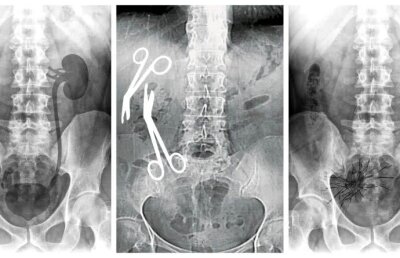

Medicul care a uitat două foarfeci într-o femeie a pierdut luni un proces după ce o altă pacientă l-a dat în judecată pentru că a găsit „două conglomerate de fire de sutură”!